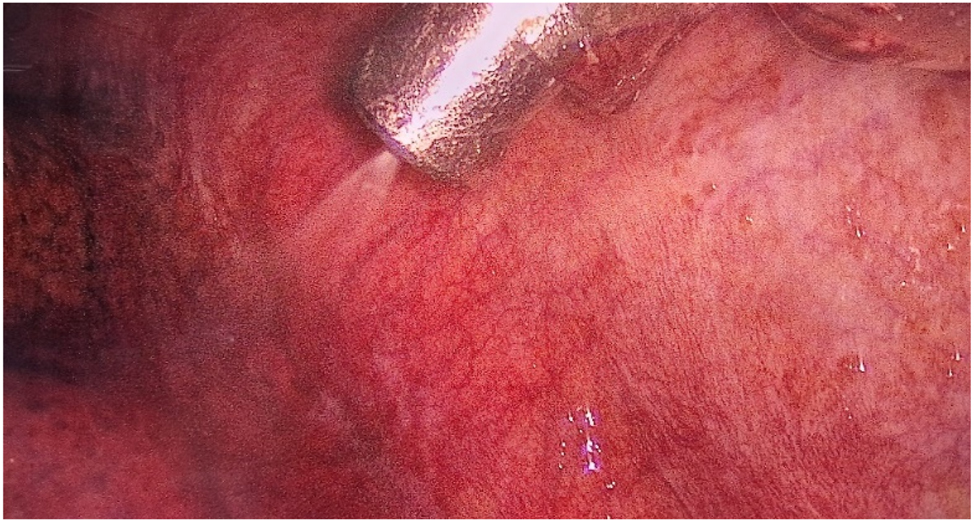

After access to the pleural cavity, MPE was evacuated. The pleural cavity was flushed with saline (pleural lavage fluid, PLF) if less than 150 mL of MPE was present. MPE or PLF was analyzed cytologically. If present, parietal PLMs were biopsied and marked by clips, and a CE-certified nebulizer was inserted through the 12 mm trocar (Figures 2 and 3).

View of the left pleural cavity during nebulization of chemotherapy.